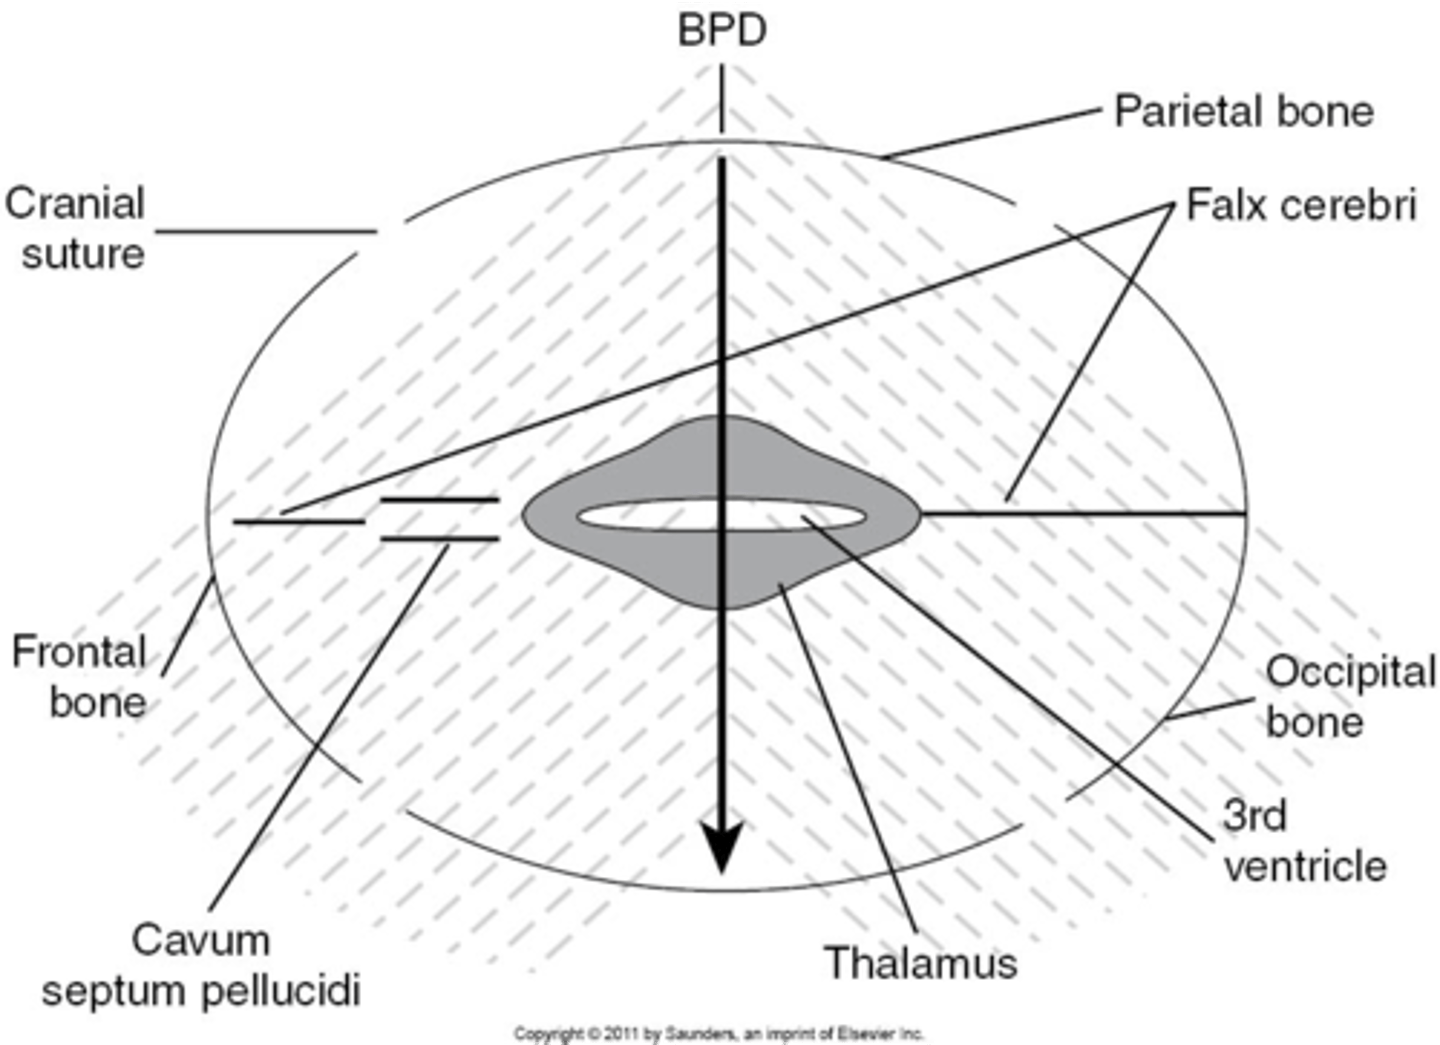

What is the most widely accepted means of measuring fetal head and estimating fetal age?

BPD

What part of the skull do you measure BPD?

midline echo complex

How do you find midline echo complex on ultrasound?

move the transducer caudally from lateral ventricles

When measuring BPD, paired ___ will be seen on either side

thalamus

When measuring BPD, what is located between the thalamus?

3rd ventricle